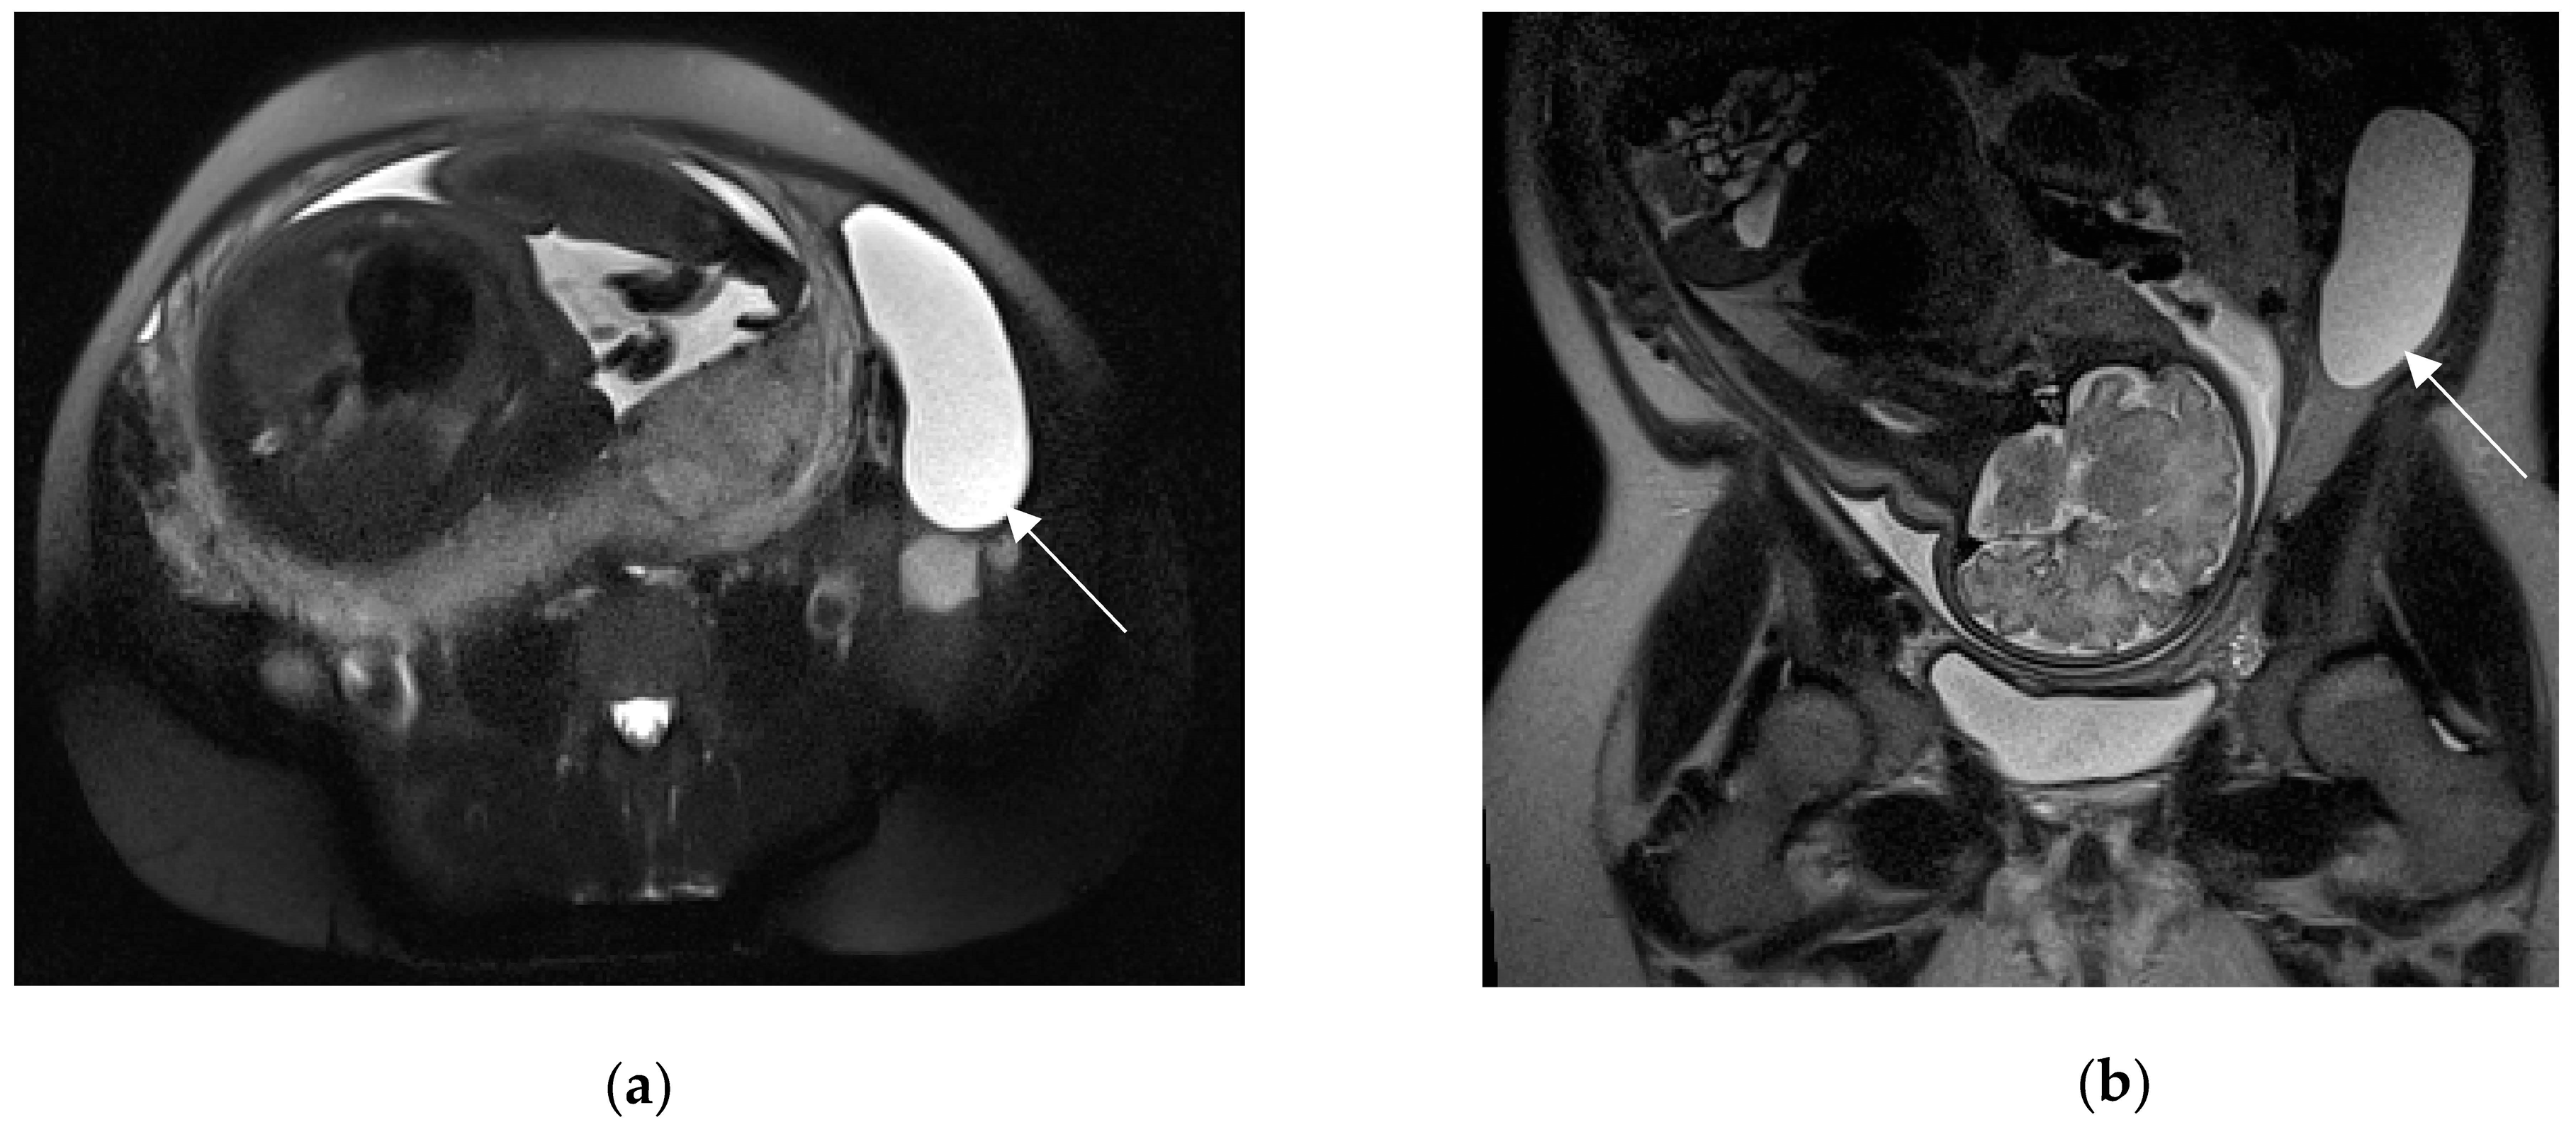

Leiomyoma with red degeneration (RDL) may show an unusual signal intensity pattern on MRI. On T1-weighted images, RDL may exhibit diffuse high-signal intensity (Figure 10) or a characteristic peripheral high-intensity rim, due to methemoglobin of blood products confined to thrombosed vessels.

Figure 10.

A 44-year-old woman at 27 weeks of gestation, known to have uterine fibroids, presented to the emergency department for acute abdominal pain. MRI shows two large and well-circumscribed pedunculated leiomyomas (arrows), characterized by a variable signal intensity on the coronal T2-weighted image (a) and diffuse high-signal intensity on the coronal T1-weighted fat-sat image (b). Findings are suggestive of haemorrhage (red degeneration). Peritoneal effusion is also depicted.

On T2-weighted images, the signal intensity may be variable with a peripheral low-intensity rim, which is also characteristic of RDL; this finding is secondary to the T2*-shortening effects of deoxyhemoglobin, intracellular methemoglobin or hemosiderin of blood products, as well as the expression of venous thrombosis [3,106,107,108]. Takeuchi et al. observed that susceptibility-weighted MR sequences (SWS), which show exquisite sensitivity to blood products, may be useful for the diagnosis of RDL by depicting a characteristic peripheral low-intensity rim [109].